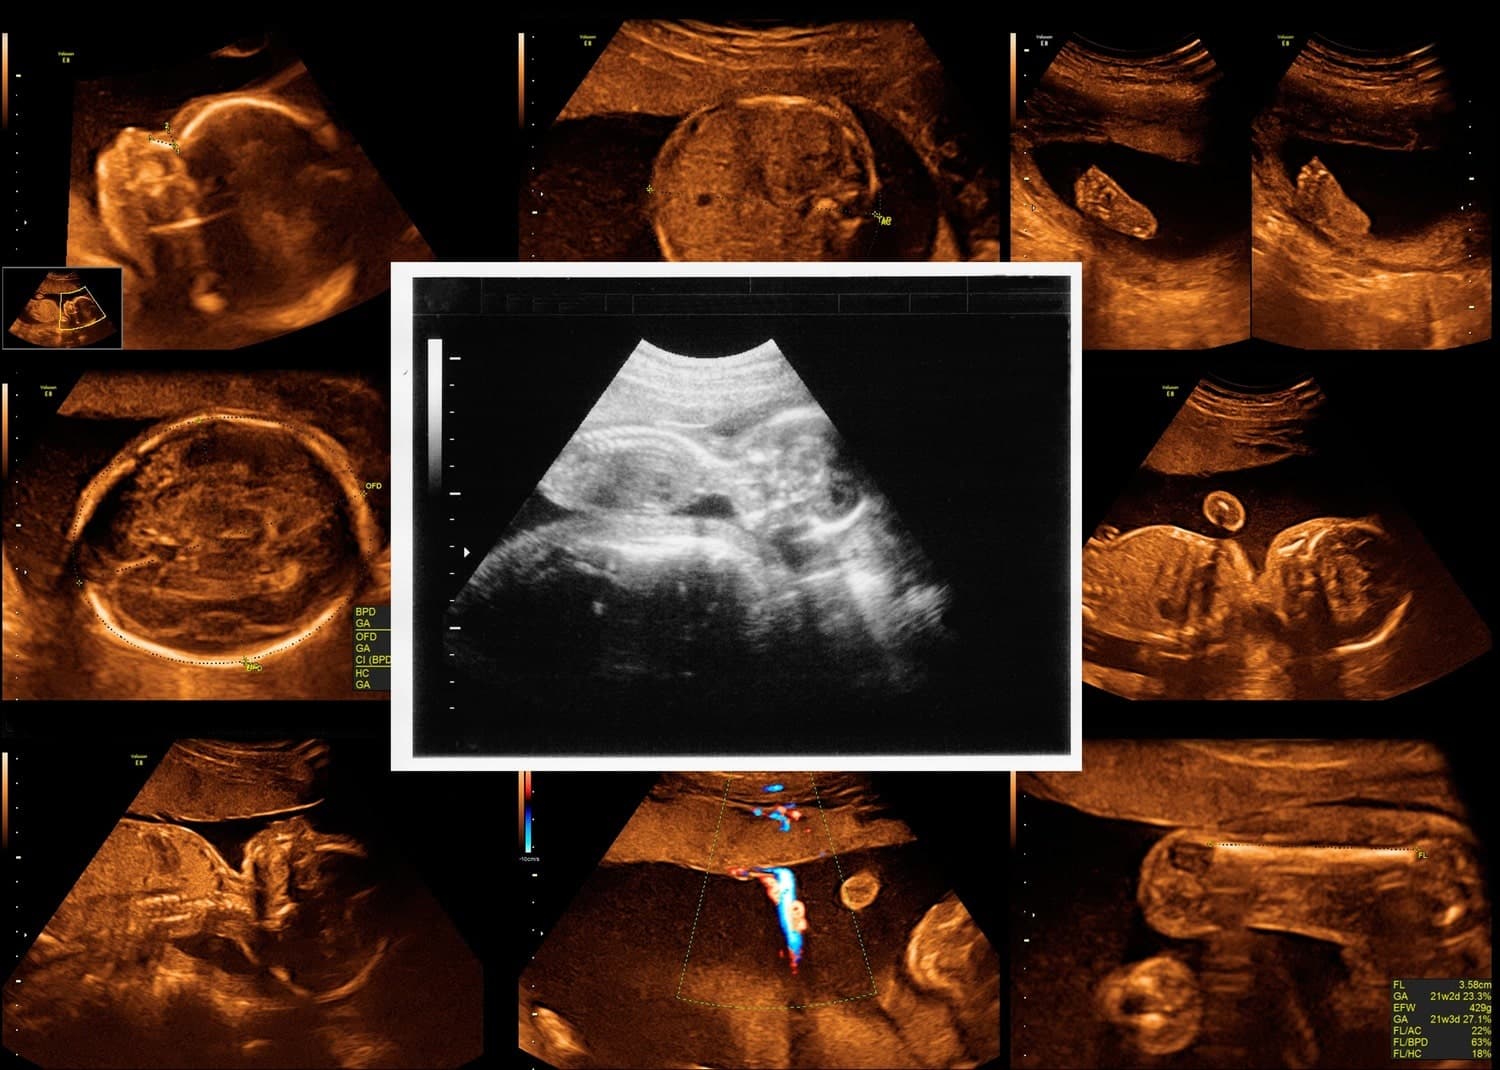

āĻ ā§āϝāĻžāύā§āĻŽāĻžāϞāĻŋ āϏā§āĻā§āϝāĻžāύ āĻšāϞ⧠āĻāϰā§āĻāĻžāĻŦāϏā§āĻĨāĻžāϝāĻŧ āĻāϰāĻž āĻāĻāĻāĻŋ āĻā§āϰā§āϤā§āĻŦāĻĒā§āϰā§āĻŖ āĻāϞā§āĻā§āϰāĻžāϏāĻžāĻāύā§āĻĄ āϏā§āĻā§āϝāĻžāύ, āϝāĻž āϏāĻžāϧāĻžāϰāĻŖāϤ ā§§ā§Ž āĻĨā§āĻ⧠⧍⧧ āϏāĻĒā§āϤāĻžāĻšā§āϰ āĻŽāϧā§āϝ⧠āĻāϰāĻž āĻšāϝāĻŧāĨ¤āĻāĻāĻŋāĻ⧠⧍ā§Ļ-āϏāĻĒā§āϤāĻžāĻšā§āϰ āϏā§āĻā§āϝāĻžāύ āĻŦāĻž āĻ ā§āϝāĻžāύāĻžāĻāĻŽāĻŋ āϏā§āĻā§āϝāĻžāύāĻ āĻŦāϞāĻž āĻšāϝāĻŧāĨ¤āĻĢāϞ⧠āĻ āύā§āĻ āĻā§āώā§āϤā§āϰ⧠āĻĒā§āϰā§ā§āĻāύā§ā§ āĻŦā§āϝāĻŦāϏā§āĻĨāĻž āύā§āĻā§āĻž āϝāĻžā§, āĻļāĻŋāĻļā§āϰ āĻāύā§āĻŽ-āĻĒāϰāĻŦāϰā§āϤ⧠āĻāϰāĻŖā§ā§ āϏāĻŽā§āĻĒāϰā§āĻā§ āĻāĻā§āĻāĻžāĻā§ āĻĒāϰāĻŋāĻāϞā§āĻĒāύāĻž āĻāϰ⧠āϰāĻžāĻāĻž āϝāĻžā§āĨ¤ āĻāϰ āĻĒāĻžāĻļāĻžāĻĒāĻžāĻļāĻŋ āĻļāĻŋāĻļā§āϰ āϏā§āĻŦāĻžāĻāĻžāĻŦāĻŋāĻ āĻŦā§āĻĄāĻŧā§ āĻāĻ āĻž āĻāĻŦāĻ āĻļāĻŋāĻļā§ āĻā§āϞ⧠āύāĻž āĻāĻŋ āĻŽā§ā§ā§âāĻāĻ āϏāĻāĻā§āϰāĻžāύā§āϤ āϤāĻĨā§āϝāĻ āĻāĻžāύāĻž āϏāĻŽā§āĻāĻŦ āĻšā§āĨ¤

ā§āϝāĻžāύā§āĻŽāĻžāϞāĻŋ āϏā§āĻā§āϝāĻžāύ āĻšāϞ⧠āĻāϰā§āĻāĻžāĻŦāϏā§āĻĨāĻžāϝāĻŧ āĻāϰāĻž āĻāĻāĻāĻŋ āĻā§āϰā§āϤā§āĻŦāĻĒā§āϰā§āĻŖ āĻāϞā§āĻā§āϰāĻžāϏāĻžāĻāύā§āĻĄ āϏā§āĻā§āϝāĻžāύ,āϝāĻž āϏāĻžāϧāĻžāϰāĻŖāϤ ā§§ā§Ž āĻĨā§āĻ⧠⧍⧧ āϏāĻĒā§āϤāĻžāĻšā§āϰ āĻŽāϧā§āϝ⧠āĻāϰāĻž āĻšāϝāĻŧāĨ¤āĻāĻāĻŋāĻ⧠⧍ā§Ļ-āϏāĻĒā§āϤāĻžāĻšā§āϰ āϏā§āĻā§āϝāĻžāύ āĻŦāĻž āĻ

āĻĒāϰā§āϝāĻŦā§āĻā§āώāĻŖ: āĻĒā§āϰā§āĻŦ āĻļāĻŦā§āĻĻ āϤāϰāĻā§āĻ āĻŦā§āϝāĻŦāĻšāĻžāϰ āĻāϰ⧠āĻāϰā§āĻā§āϰ āĻļāĻŋāĻļā§āϰ āϏā§āĻā§āϰāĻŋāύ⧠āĻāĻŦāĻŋ āϤā§āϰāĻŋ āĻāϰā§āĨ¤ āϏā§āύā§āĻā§āϰāĻžāĻĢāĻžāϰ āĻāĻ āĻāĻŦāĻŋ āĻĻā§āĻā§ āĻļāĻŋāĻļā§āϰ āĻŽāϏā§āϤāĻŋāώā§āĻ, āĻšā§āĻĻāĻĒāĻŋāĻŖā§āĻĄ, āĻŽā§āϰā§āĻĻāĻŖā§āĻĄ, āĻŽā§āĻāĻŽāĻŖā§āĻĄāϞ, āĻāĻŋāĻĄāύāĻŋ, āĻĒā§āĻ āĻāĻŦāĻ āĻ āĻā§āĻ-āĻĒā§āϰāϤā§āϝāĻā§āĻ āϏāĻš āĻļāϰā§āϰā§āϰ āĻŦāĻŋāĻāĻŋāύā§āύ āĻ āĻāĻļ āĻĒāϰā§āĻā§āώāĻž āĻāϰā§āύ āĻāĻŦāĻ āϏā§āĻā§āϞāĻŋāϰ āĻĒāϰāĻŋāĻŽāĻžāĻĒ āύā§āύāĨ¤ āĻļāĻŋāĻļā§āϰ āĻā§āύ⧠āĻāύā§āĻŽāĻāϤ āϤā§āϰā§āĻāĻŋ āĻŦāĻž āĻ āϏā§āĻŦāĻžāĻāĻžāĻŦāĻŋāĻāϤāĻž āĻāĻā§ āĻāĻŋāύāĻž āϤāĻž āĻĻā§āĻā§āύāĨ¤

āĻ ā§āϝāĻžāύā§āĻŽāĻžāϞāĻŋ āϏā§āĻā§āϝāĻžāύā§āϰ āϏāĻŽā§ā§ āĻļāĻŋāĻļā§āϰ āĻŽā§āĻāĻŽāĻŖā§āĻĄāϞ, āĻšāĻžāϤ-āĻĒāĻž, āĻĒā§āĻ āĻ āύāĻžāĻĄāĻŧāĻŋāĻā§āĻāĻĄāĻŧāĻŋ, āĻšāĻžāĻĄāĻŧ, āĻšāĻžāϰā§āĻ, āĻāĻŋāĻĄāύāĻŋ, āĻŦā§āϰā§āĻāύ āĻ āϏā§āύāĻžā§ā§āϤāύā§āϤā§āϰ āĻā§āĻāĻāĻŋā§ā§ āĻā§āĻāĻāĻŋā§ā§ āĻĻā§āĻāĻž āĻšā§āĨ¤ āĻāĻ āϏā§āĻā§āϝāĻžāύ⧠āĻāύā§āĻŽāĻāϤ āϤā§āϰā§āĻāĻŋ āĻŦāĻž âāĻ ā§āϝāĻžāύā§āĻŽāĻžāϞāĻŋâ āĻŦā§āϰ āĻāϰāĻžāϰ āĻĒāĻžāĻļāĻžāĻĒāĻžāĻļāĻŋ āĻ āύā§āĻāĻā§āϞ⧠āϤāĻĨā§āϝ āĻĒāĻžāĻā§āĻž āϝāĻžā§āĨ¤ āϝā§āĻŽāύâ

āĻ ā§āϝāĻžāύā§āĻŽāĻžāϞāĻŋ āϏā§āĻā§āϝāĻžāύ (Anomaly Scan), āϝāĻž āĻāϞāĻā§āϰāĻžāϏāĻžāĻāύā§āĻĄ āϞā§āĻā§āϞ ⧍ āĻŦāĻž ⧍ā§Ļ-āϏāĻĒā§āϤāĻžāĻšā§āϰ āϏā§āĻā§āϝāĻžāύ āύāĻžāĻŽā§āĻ āĻĒāϰāĻŋāĻāĻŋāϤ, āĻāĻāĻŋ āĻāϰā§āĻāϏā§āĻĨ āĻļāĻŋāĻļā§āϰ āĻāύā§āĻŽāĻāϤ āϤā§āϰā§āĻāĻŋ āĻŦāĻž āĻ āϏā§āĻŦāĻžāĻāĻžāĻŦāĻŋāĻāϤāĻž āύāĻŋāϰā§āĻŖā§ā§āϰ āĻāύā§āϝ āĻāĻāĻāĻŋ āĻā§āϰā§āϤā§āĻŦāĻĒā§āϰā§āĻŖ āĻāĻŦāĻ āϏāĻžāϧāĻžāϰāĻŖāϤ āύāĻŋāϰā§āĻāϰāϝā§āĻā§āϝ āĻĒāϰā§āĻā§āώāĻžāĨ¤

āϏā§āĻŦāĻžāĻāĻžāĻŦāĻŋāĻāϤāĻž āĻā§āĻāĻā§ āĻŦā§āϰ āĻāϰāĻžāϰ āĻā§āώā§āĻāĻž āĻāϰāĻž āĻšāϝāĻŧāĨ¤ āĻāĻ āϏā§āĻā§āϝāĻžāύ⧠āϝā§āϏāĻŦ āĻāύā§āĻŽāĻāϤ āϤā§āϰā§āĻāĻŋ āϧāϰāĻž āĻĒā§āϤ⧠āĻĒāĻžāϰā§, āϤāĻžāϰ āĻŽāϧā§āϝ⧠āĻāĻŋāĻā§ āĻĒā§āϰāϧāĻžāύ āϤā§āϰā§āĻāĻŋ āύāĻŋāĻā§ āĻāϞā§āϞā§āĻ āĻāϰāĻž āĻšāϞā§: